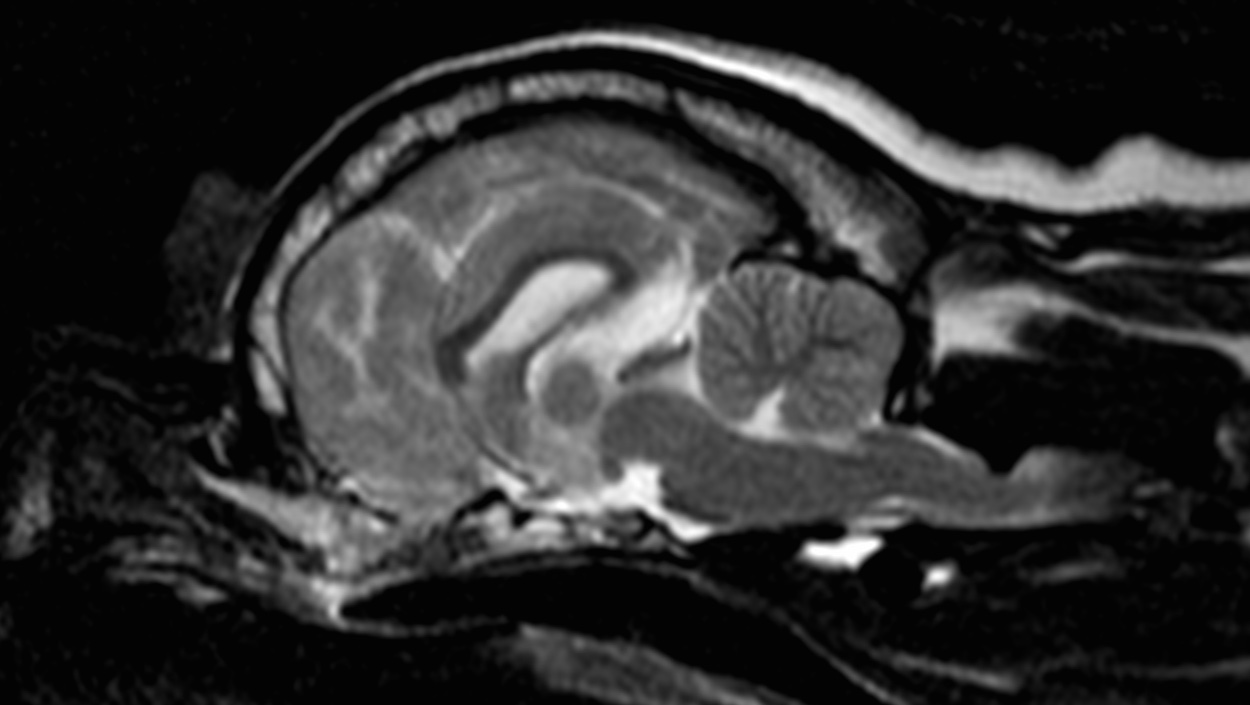

При проведении мрт выявлена дорсальная компрессия спинного мозга в сегменте между первым и вторым шейными позвонками. Это врожденная аномалия краниовертебрального перехода

Данная патология носит название впадина Дьюи